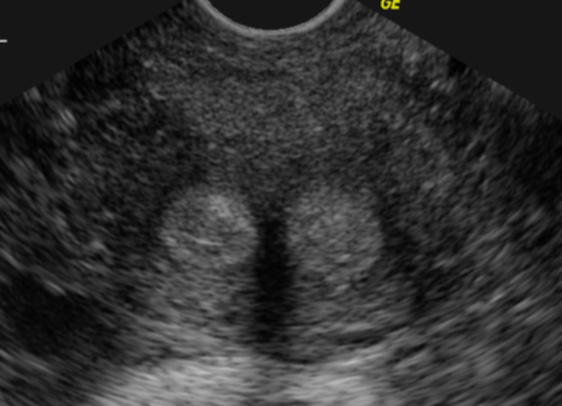

Utérus cloisonné (coupe transversale) (Cliché : Dr. C. TALMANT)